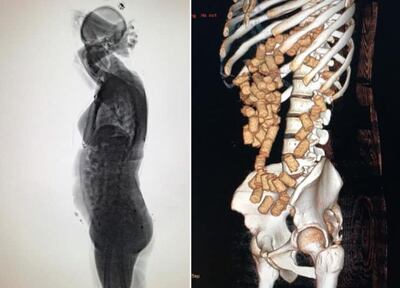

La droga fue detectada por los agentes de la Policía Federal del Brasil al momento en que la joven ingresó al escáner del aeropuerto. Esto, antes de que la compatriota intentara abordar un vuelo que tenía como destino San Pablo y donde debía tomar otro que la llevaría hasta la ciudad de Valencia, en España.

De acuerdo con el informe, se pudieron contabilizar un total de 87 cápsulas que en su interior contenían cocaína y que llevaba ella en el estómago.

Así también, se logró detectar otro paquete de 300 gramos que llevaba escondido en sus partes íntimas.